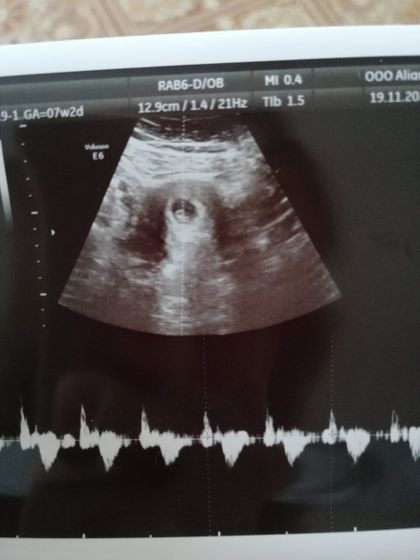

Наверно, получится длинный пост. Сходили с мужем на узи в Альянс Клиник, к моей любимой Блиновой. Мужа пустили) увидели нашу кроху, вчк хорошо, тонуса нет, сказали поменьше тяжести поднимать. Ктр 4,8 мм. Сердечко 134 удара) по месячным сегодня 7,2 нед, но узи 6,1. Но это не страшно) ну и самый главный вопрос мой был- длина шейки, тк в первую беременность был ицн и стоял пессарий. Шейка 29 мм. Врач сказала в 80% случаев ицн повторяется. Сказала до 12 недель малыша не трогать, в 12 на скрининг, там попросить шейку измерить и потом ещё в 16 недель и уже на основании этого будут решать что делать. Будем надеяться, что все будет хорошо. Самое главное, сердечко бьётся и с малышом все хорошо)),